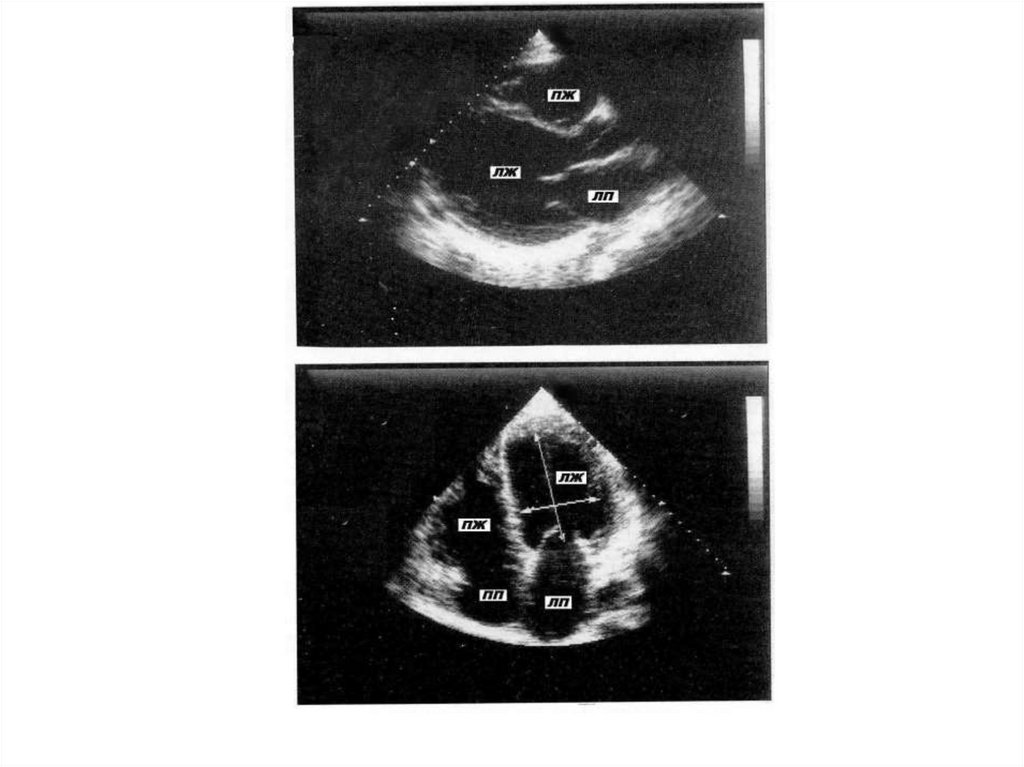

16. ДИЛАТАЦИОННАЯ КАРДИОМИОПАТИЯ (ДКМП)

ДКМП представляет собой заболевание

миокарда, характеризующееся

дилатацией камер сердца и

прогрессирующим снижением

сократимости миокарда.

40. ЭхоКГ изменения при остром МКТ:

а) лёгкое течение:

• ЭхоКГ картина может быть нормальной; или

• небольшая дилатация полости и дисфункция ЛЖ (снижение

систолической экскурсии стенок, небольшое снижение ФВ);

б) тяжёлое течение:

• резкое снижение ФВ;

• может быть снижение сократимости сегментарного характера;

• несоответствие между резко выраженным снижением

сократимости и небольшой степенью дилатации полостей

(отличие от ДКМП);

• обратимое увеличение толщины стенок ЛЖ (отёк);

• пристеночные тромбы в полости ЛЖ на фоне гипокинезии

миокарда и эндокардита;